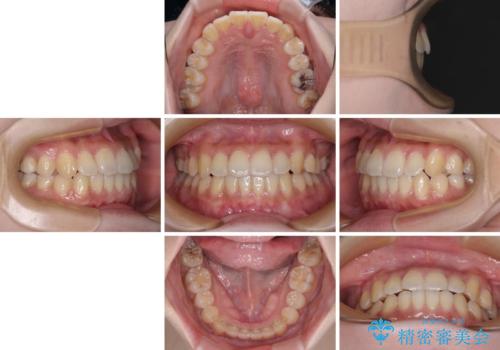

- 八重歯や前歯の捻転とクロスバイトが気になり、インビザラインによる矯正治療を希望して来院された患者様です。

上顎側切歯(上の真ん中から2番目の歯)が舌側転位している場合、無理して動かそうとすると歯髄壊死を起こすリスクが高い印象があります。

インビザライン単体でも治療は可能ですが、安全策としてインビザラインで歯列を移動する前に上顎前歯をワイヤー矯正で整え、その後上下歯列をインビザラインにて矯正治療を行うこととしました。

舌側転位している側切歯特有の、切縁の位置が不揃いであったり、根元が内側に引っ込んだ状態であったりという、インビザライン独特の仕上がりになることなく、きれいに整った歯列とすることができました。